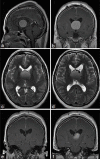

Background: Colloid cysts are usually located at the rostral part of the third ventricle in proximity to the foramina of Monro. Some third ventricular colloid cysts, however, attain large sizes, reach a very high distance above the roof of the third ventricle, and pose some challenges during endoscopic excision. These features led to the speculation that for such a pattern of growth to take place, the points of origin of these cysts should be at areas away from the foramina of Monro at which some anatomical "windows" exist that are devoid of compact, closely apposed forniceal structures.

Results: Colloid cysts may grow vertically up past the roof of the third ventricle through anatomical windows devoid of the mechanical restraint of the forniceal structures.

Conclusion: Some anatomical variations of the forniceal structures may allow unusually large sizes and superior vector of growth of a retro- or post-foraminal colloid cyst. Careful preoperative planning and knowledge of the pertinent pathoanatomy of these cysts before endoscopic excision is very important to avoid complications.